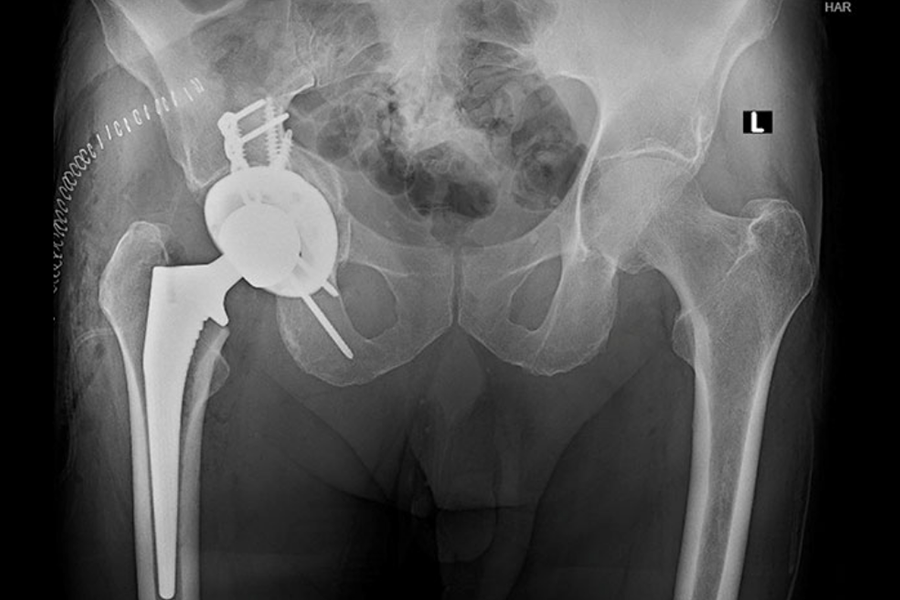

Time to Surgery Impact on Geriatric Patients with Hip Fractures

Nicholas C. Danford, MD, an orthopedic surgeon at NewYork‑Presbyterian and Columbia, conducted a study assessing how the time from hospital admission to surgery impacts postoperative complications and mortality for patients with acetabular fractures, particularly older adults. The study’s results underscored the importance of time to surgery, showing that shorter time between admission and surgery is associated with fewer complications; less than 5% of patients experienced complications if they had surgery within two days of admission, and the likelihood of a complication increased by 7% with each day after admission. If a patient is healthy enough to undergo surgery, the results of this study support the practice of optimizing surgery timing for patients with acetabular fractures.

Patient who underwent surgical treatment of a geriatric acetabular fracture.